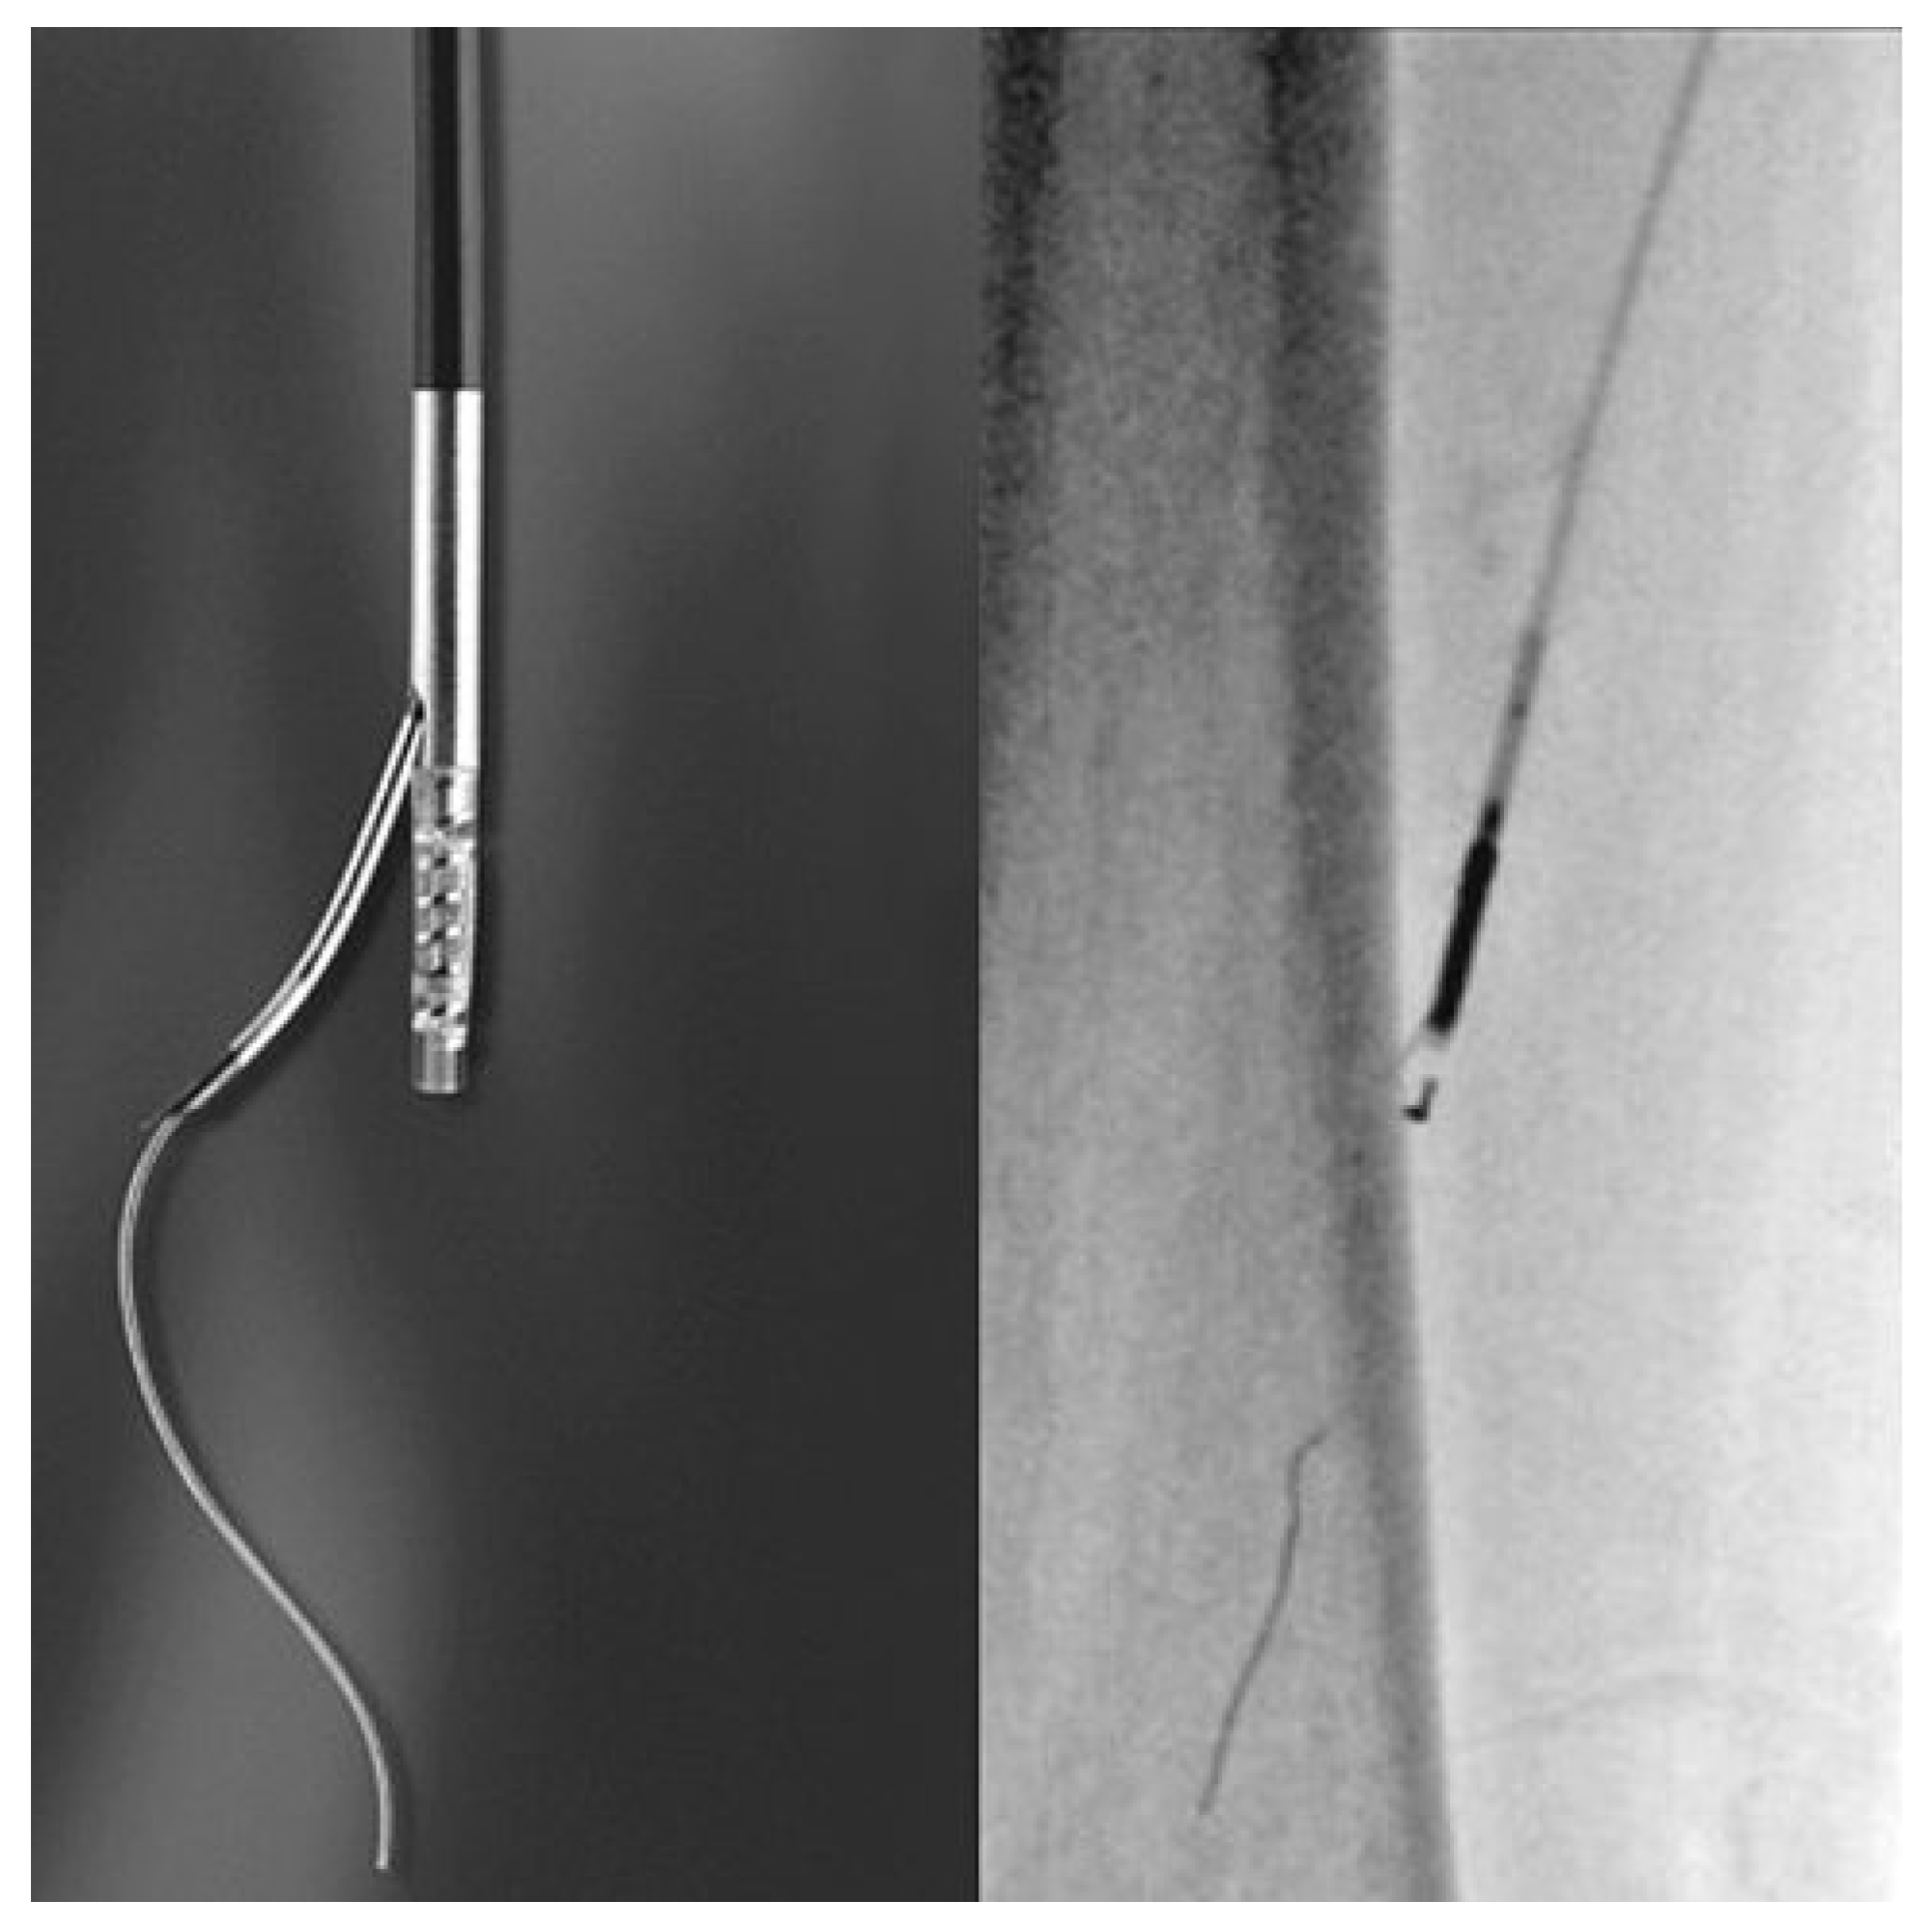

Une avancée dans le monde interventionnel, surtout en ce qui concerne la recanalisation sous-intimale des longues occlusions fémorales, est l’apparition depuis quelques années, des «reentry devices»: Le Outback™ (Cordis, Miami, FL, Etats-Unis, Figure 2) [5] et le Pioneer™ (Medtronic, Santa Rosa, CA, Etats-Unis) [20]. L’avantage de ce type de cathéter est qu’ils permettent de pouvoir rétablir de façon rapide la connexion entre l’espace sous-intimal et la vraie lumière en réduisant par conséquence à <10% le taux d’échec des recanalisations des longues occlusions des artères fémorales [5,24].

Figure 2. Outback™ Reentry Catheter (Cordis, Miami, FL, Etats-Unis).